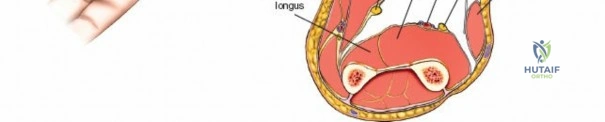

A thorough understanding of forearm anatomy is paramount for safe and effective fasciotomy. The forearm is typically divided into four primary osseo-fascial compartments, although some classifications may describe five:

- Superficial Volar (Flexor) Compartment: Contains pronator teres, flexor carpi radialis (FCR), palmaris longus, flexor carpi ulnaris (FCU), and flexor digitorum superficialis (FDS). The median nerve and ulnar artery course deep to this compartment, but their branches may be superficial. The fascia overlying this compartment is robust.

- Deep Volar (Flexor) Compartment: Deep to the FDS, this compartment houses flexor digitorum profundus (FDP), flexor pollicis longus (FPL), and pronator quadratus (PQ). The anterior interosseous nerve (AIN), a branch of the median nerve, and the anterior interosseous artery (AIA), a branch of the ulnar artery, are key structures here. The median nerve, deep to the FDS, is a critical structure that requires protection. The ulnar nerve and artery run along the ulnar border.

- Dorsal (Extensor) Compartment: Contains the extensor carpi ulnaris (ECU), extensor digiti minimi (EDM), extensor digitorum communis (EDC), and supinator. The posterior interosseous nerve (PIN), a branch of the radial nerve, courses through the supinator and then becomes the primary innervation for the dorsal compartment musculature.

- Lateral (Mobile Wad) Compartment: Also known as the mobile wad of Henry, this compartment contains the brachioradialis (BR), extensor carpi radialis longus (ECRL), and extensor carpi radialis brevis (ECRB). The superficial radial nerve runs deep to the brachioradialis in its distal third.

I. Volar (Anterior) Approach

The volar approach addresses the superficial and deep volar compartments, which are most commonly involved and contain the majority of the forearm musculature and critical neurovascular structures.

Incision: A curvilinear incision is made from the medial epicondyle, across the antecubital fossa, extending obliquely to the mid-volar aspect of the forearm, and then longitudinally down to the wrist crease, potentially extending into the palm to release the carpal tunnel. The incision should be generous, allowing for wide exposure.

- Key points: The proximal portion of the incision should curve gently to avoid crossing the elbow flexion crease at a right angle, which could lead to contracture. Distally, it should avoid cutting directly over the median nerve at the wrist.

This image shows the standard curvilinear incision for the volar approach, extending proximally from the medial epicondyle, gently crossing the antecubital fossa, and proceeding distally across the mid-forearm to the wrist.

- Key points: The proximal portion of the incision should curve gently to avoid crossing the elbow flexion crease at a right angle, which could lead to contracture. Distally, it should avoid cutting directly over the median nerve at the wrist.